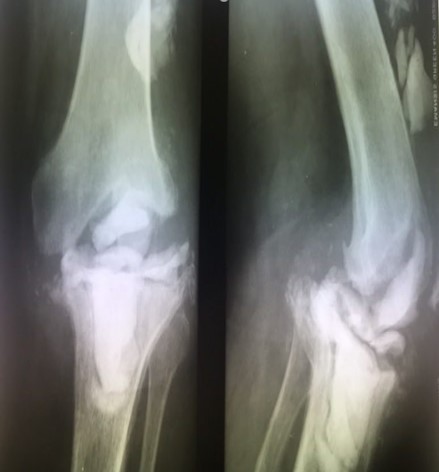

Приклад 1. Хвора Б. 52 років. Діагноз: Ревматоидній Деформівний IVст. гонартроз, вальгусна деформація колінногосуглоба.  Нестабільність та руйнування компонентів ендопротеза. Хворій виконано ревізійне ендопротезування: видалення компонентів ендопротезу, виявлений дефект латерального  виростку великогомілкової кістки тип Т3А за класифікацією АОRI [G.A. Engh, C.H. Rorabeck, 1997]. Під час операції виконана кісткова пластика дефекту латерального виростка лівої великогомілкової кістки. Використаний ендопротез колінного суглоба з подовжувачами .